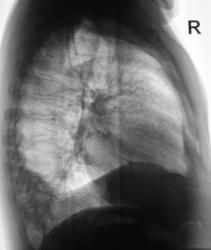

Пациент был направлен в рентгеновский кабинет терапевтом с диагнозом "Правостороняя пневмония". Было произведено стандартное исследование.

Было назначено противовоспалительное лечение. Через 1 неделю проведен "рентген-контроль".